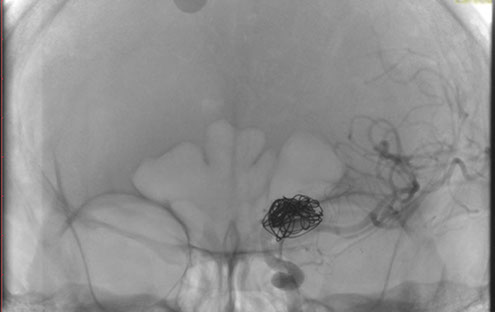

La paciente ingreso al Servicio de Hemodinamia el día martes 11 de febrero con un aneurisma cerebral gigante en la carótida izquierda y se le practicó una embolización; es decir una oclusión por dentro del mismo, donde se colocó un dispositivo denominado coils más un stent diversor de flujo. El procedimiento fue exitoso y contó con la colaboración de médicos neurointervencionistas del Instituto Oulton de la Ciudad de Córdoba.